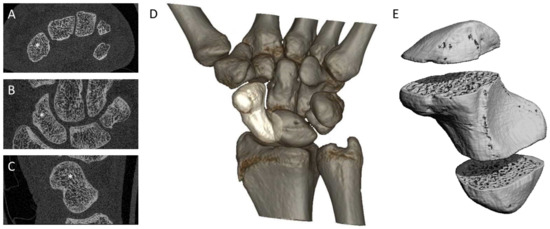

2.3. Image Quality Grading